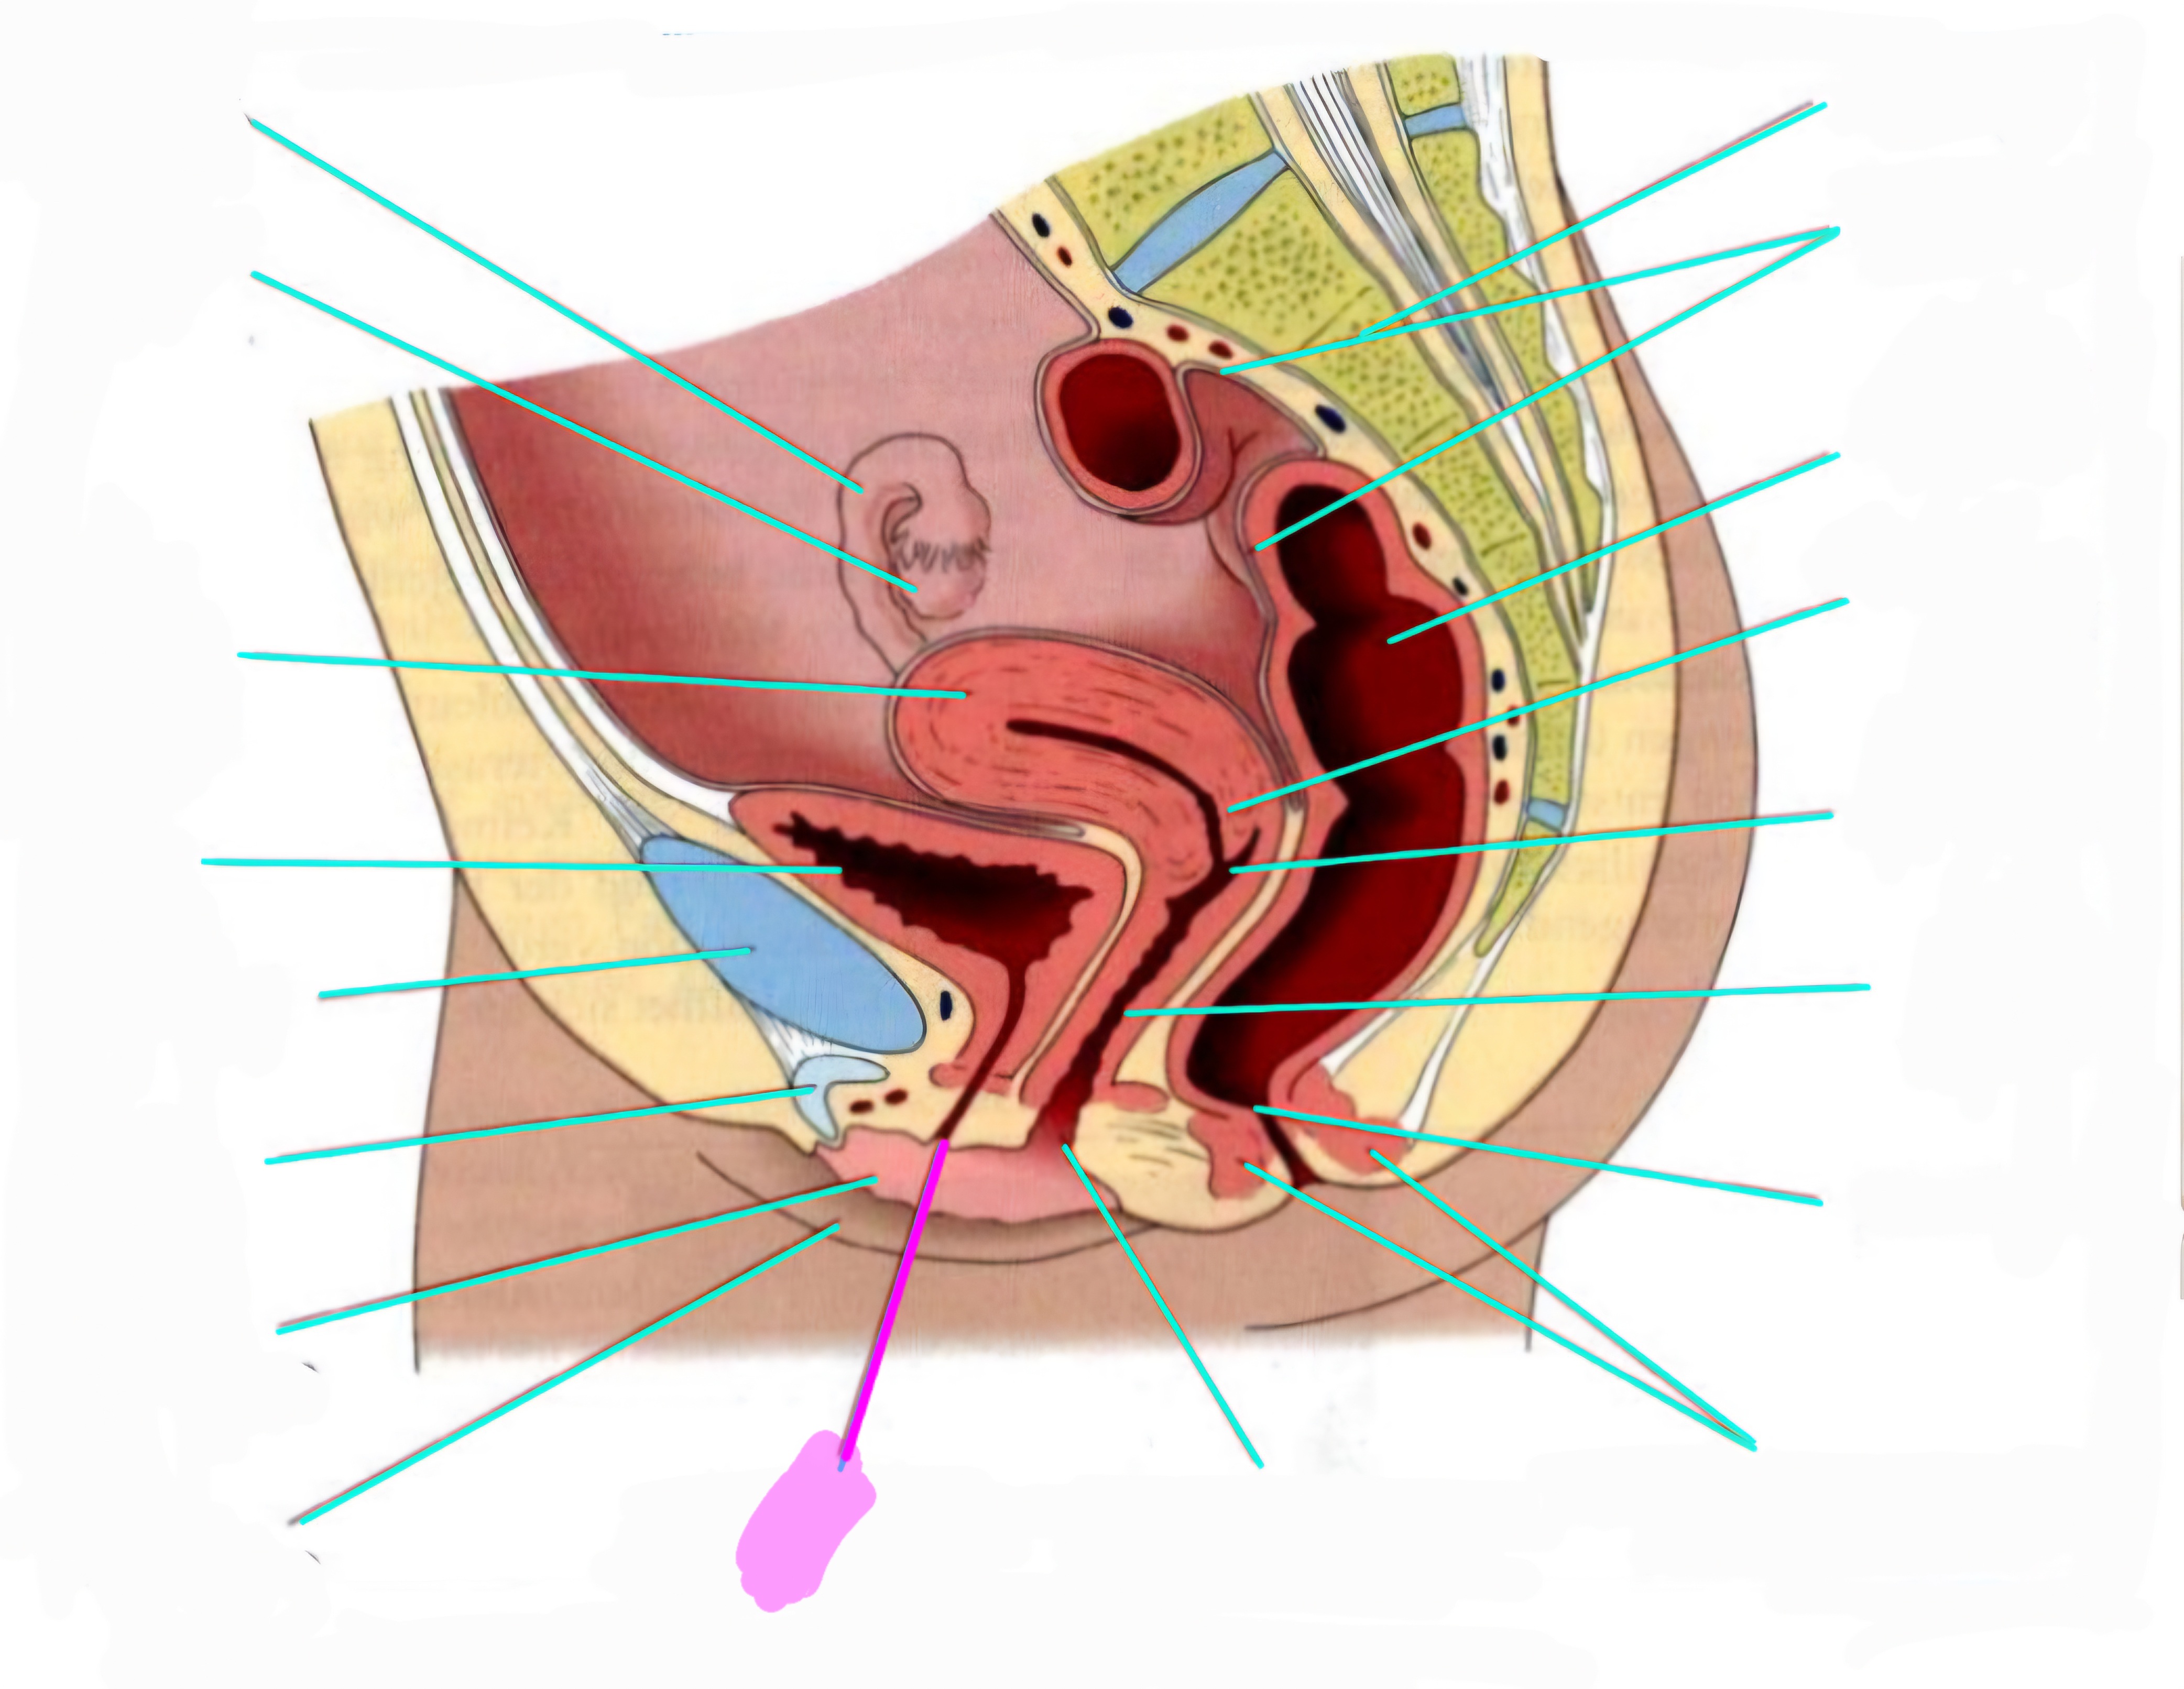

wbl. genital Anatomie

19 Terms

Tubea uterina (Eileiter)

Ovar (Eierstock)

Uterus (Gebärmutter)

Vesica Urinaria (Harnblase)

Symphyse

Klitoris

Labia minor pudendi (kleine schamlippen)

Labia Majoran pudendi (große Schamlippe)

Urethra (Harnröhre)

Introitus vaginae (Scheideneingang)

Sphincter ani externes (äußere Afterschließmuskel)

Anus (After)

Vagina (Scheide)

Portio (äußerer Muttermund)

Rektum (Mastdarm)

Zervix (Gebärmutterhals)

Peritoneum (Bauchfell)

Os sacrum (Kreuzbein)